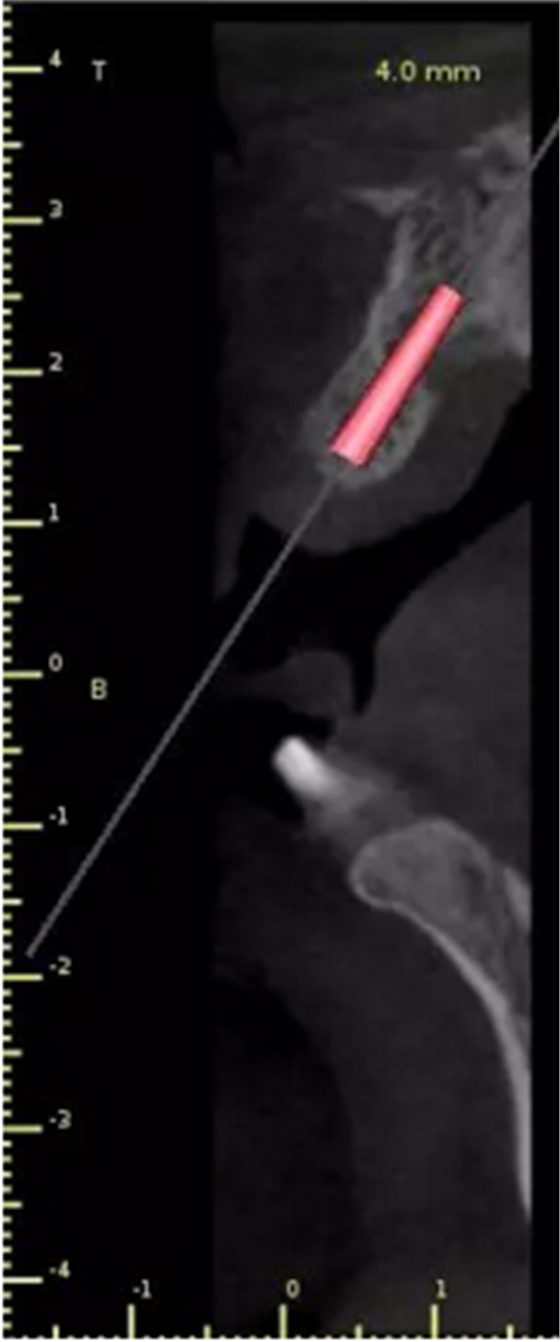

1.術(shù)前CT

2.術(shù)前植體設(shè)計(jì)

3.術(shù)前導(dǎo)板設(shè)計(jì)